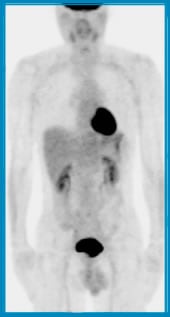

低分化がんや未分化がんのPET画像をとると、それらのがんは高分化がんに比べ細胞分裂が活発であるためFDGの集積が高く、濃い画像となります。

FDGは、体内に投与されたあと尿として排泄されるため肝臓や膀胱、尿路に集積します。また、脳や心臓はそもそもブドウ糖をエネルギー源として多量に摂取するため、FDGの取り込みはがん細胞の存在の有無に関わらず多くなります。したがって、これらの部位に存在するがんを見つけることは難しいと考えられます。